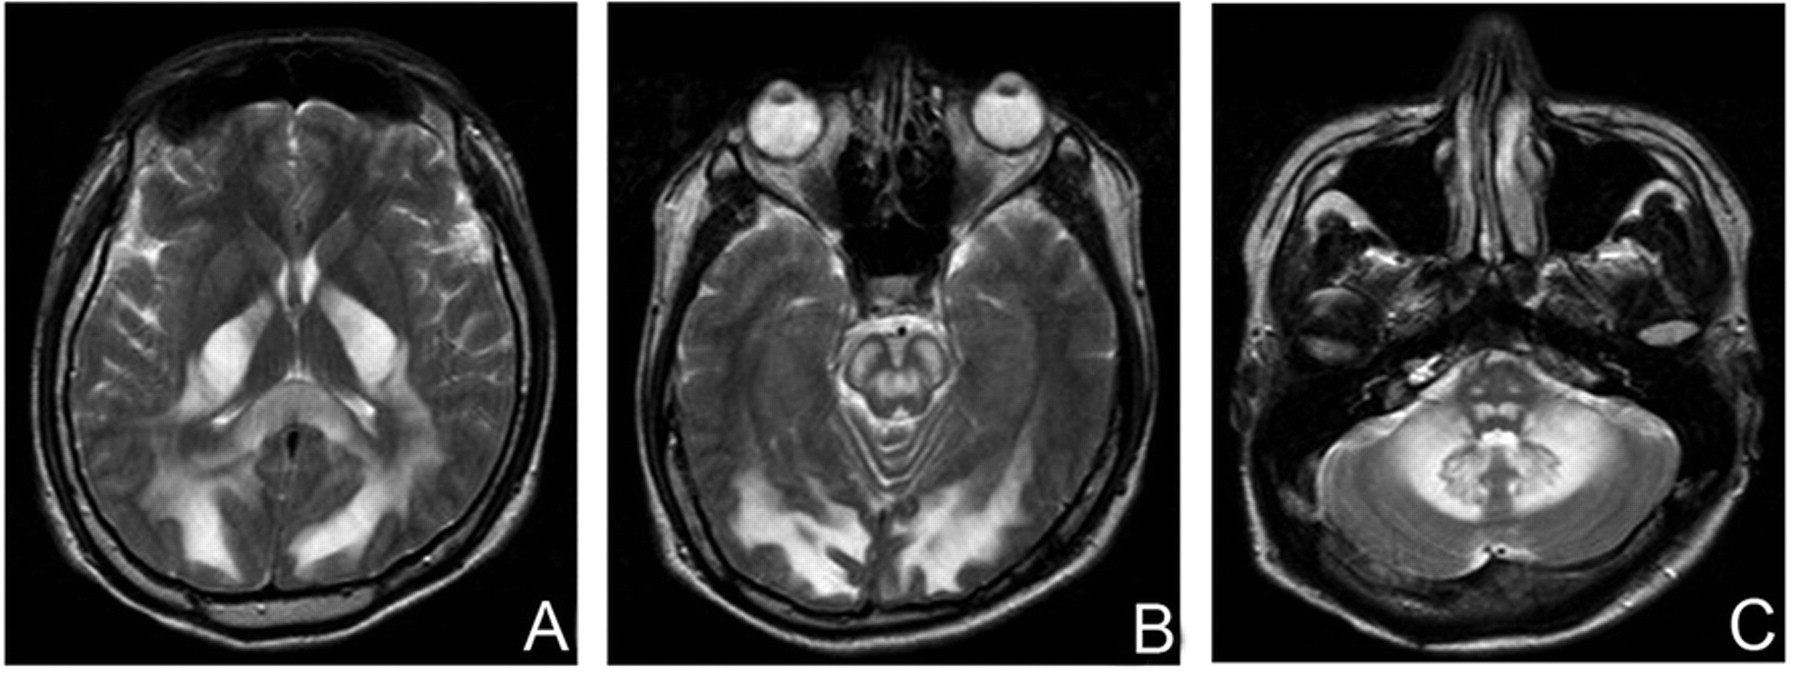

图1所示。轴向t2加权图像先生(重复时间/回波时间:4000/99)对称hyperintensity受影响的大脑(A)后,脑桥(B)和小脑白质(C)。大脑皮层、基底神经节和花托幸免于难。

t2加权MRI显示对称hyperintensity白质束符合海绵状变性和髓鞘脱失(图1)。1参与这些白质束和内囊后肢,抽出的皮层和基底神经节,在heroin-induced特征发现脑白质病,有助于区别于其它原因造成的脑白质病。1H夫人透露N-acetylaspartate /肌酐下降(乙酰天冬氨酸/ Cr)比和紧身上衣乳酸峰(图2),表明线粒体功能障碍和神经毒性。2MRI可以准确揭示白质异常的分布heroin-induced患者脑白质病,和1H夫人,虽然不是必不可少的诊断,有助于进一步阐明条件。